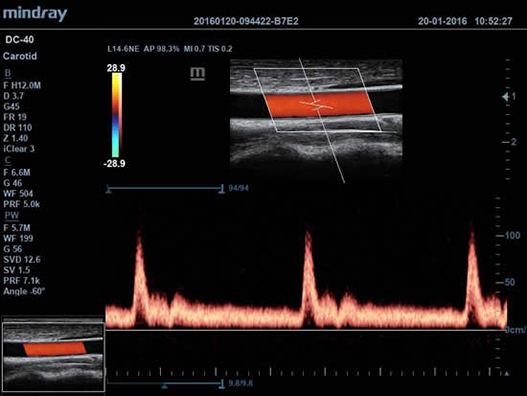

• Импульсно-волновой доплер (PW), включая режим доплеровского сканирования с высокой частотой повторения импульсов (HPRF);

• Цветной доплер (Color Doppler);

• TDI (Tissue Doppler imaging, including TDI Color, Power, PW and M mode) – пакет тканевой допплерографии, включая цветное картирование, импульсный тканевой допплер, энергетический тканевой допплер и тканевой М-режим;